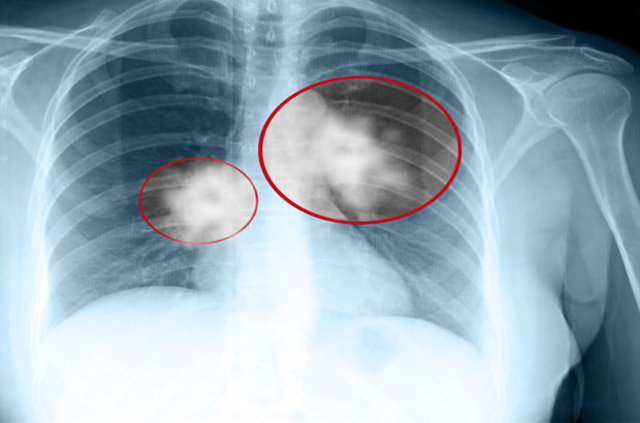

Dünyada hayati tehlikeye en fazla neden olan kanser türü olarak bilinen akciğer kanseri, vücutta meydana gelen küçük değişikliklerin önemsenmesiyle erken dönemde teşhis edilebiliyor. Belirtileri tanımak ve akciğer kanserinin en önemli nedeni olan sigaradan uzak durmak, hastalıkla mücadelede çok büyük bir rol oynuyor.

Günümüzde kanser vakalarına bakıldığında kalın bağırsak, meme ve prostat kanseri nedeniyle yaşamını yitirenlerin toplamından daha fazla kişi akciğer kanseri nedeniyle hayatını kaybediyor.